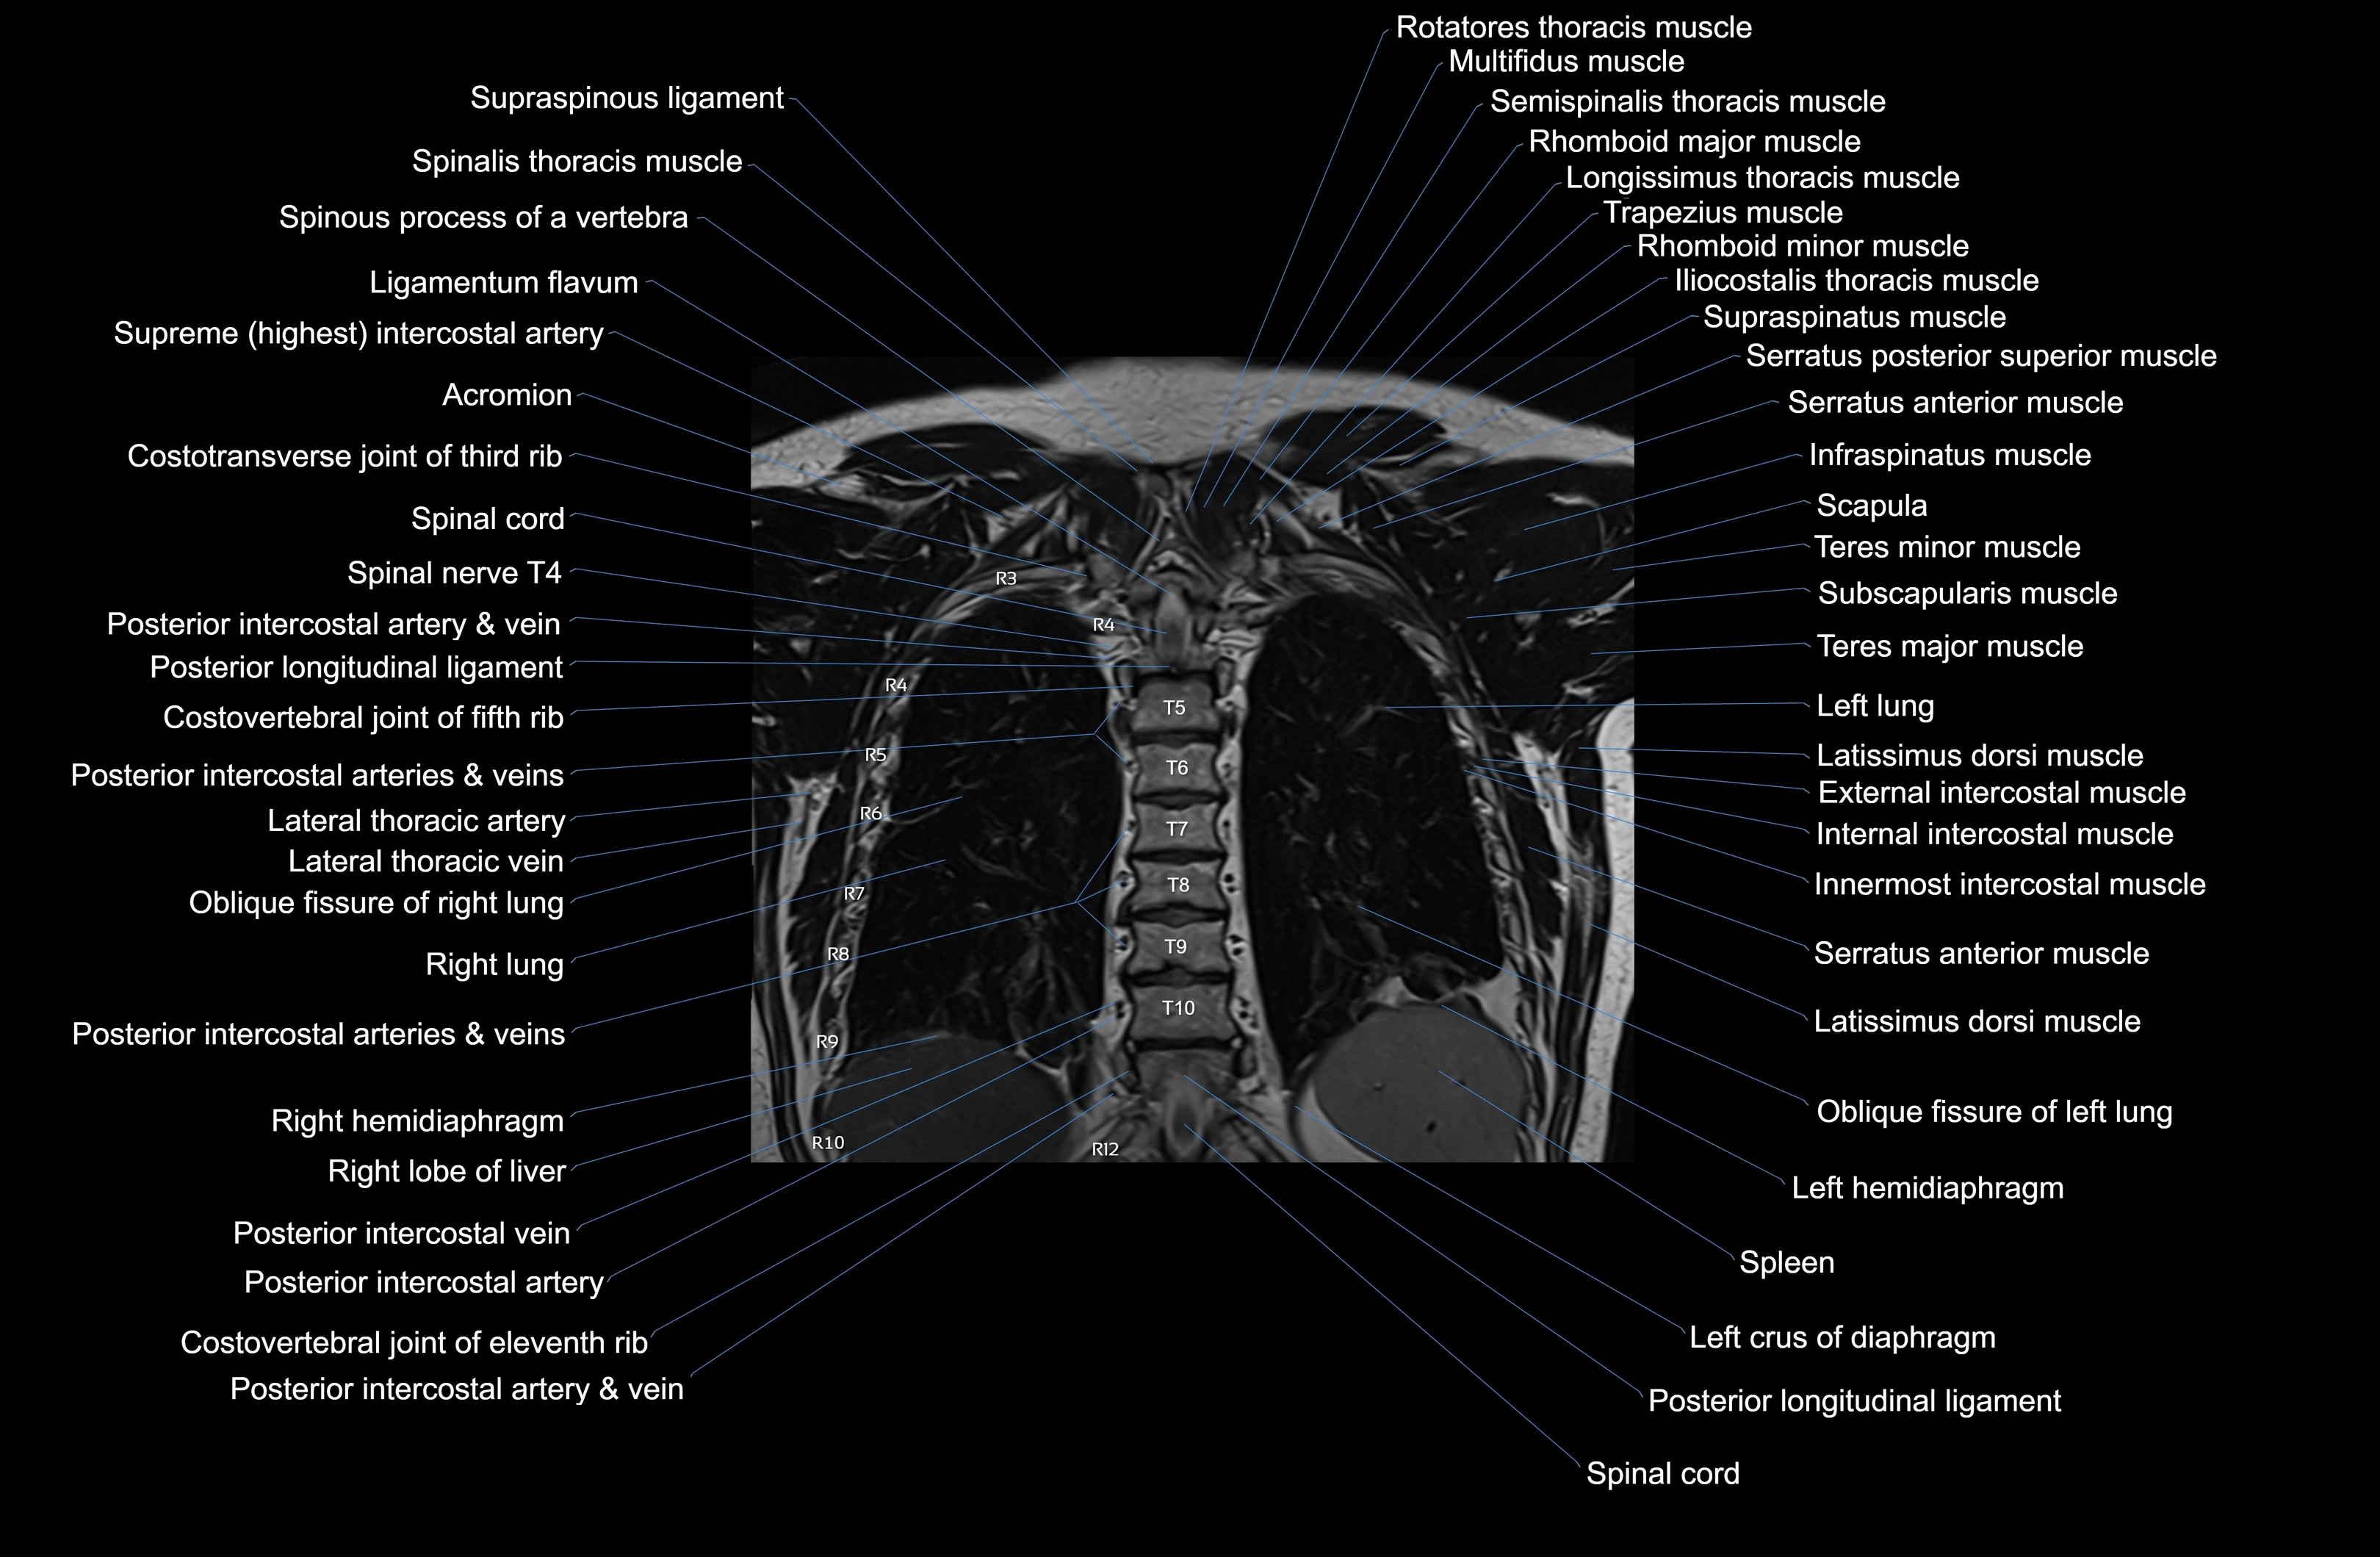

MRI images